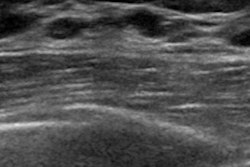

Editor's note: The image on the home page is a virtual touch tissue imaging quantification image of a healthy breast showing fatty tissue (1.38 m/sec) and parenchyma (3.33 m/sec). Image courtesy of Dr. Michael Golatta.